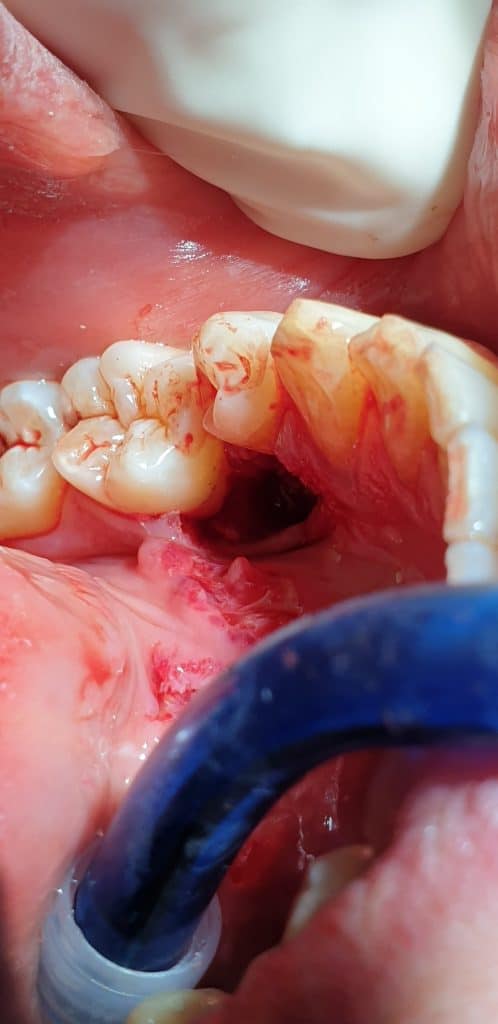

L’avulsione ha presentato un discreto livello di difficoltà vista la posizione e lo stretto rapporto col 3.4, tanto da ipotizzare l’avulsione anche del 3.4.

L’estrazione è stata portata a termine con successo, il dente ha presentato radice curva e nella zona interessata dell’estrazione si è provveduto a inserire spugnetta emostatica ed osso sintetico e sutura.